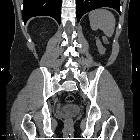

Seminal vesicle agenesis is a condition that refers to the congenital absence of one or both seminal vesicles.

Seminal vesicle agenesis is a rare finding with a reported incidence of 0.08 % .

Unilateral or bilateral absence of seminal vesicles, posterior to the prostate.